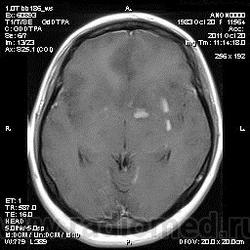

Эта же пациентка... Июль 2011 года....

В анамнезе есть зацепки на энцефалит?Мне ни разу не встречался, поэтому умничать не буду.

А здесь вариант Арнольда-Киари+ платибазия к тому же (?)

мне кажется больше похоже на диффузную глиальную опухоль. Для герпетического нехарактерна локализация и характер контрастирования. Хотя конечно нет правил без исключений..

Евгений Второй, а медиобазальные отделы височных долей - по-моему излюбленная локализация герпетических энцефалитов... Да мне кажется, что серое и белое вещество в равной степени вовлечено в процесс...

Арнольда-Киари можно указать, но вы же понимаете, что он меркнет на фоне основной патологии....

а медиобазальные отделы височных долей - по-моему излюбленная локализация герпетических энцефалитов..

Абсолютно согласен, просто у меня не все картинки раньше загрузились и показалось, что все изменения в лобных долях и базальных ядрах. Снимаю свои возражения.